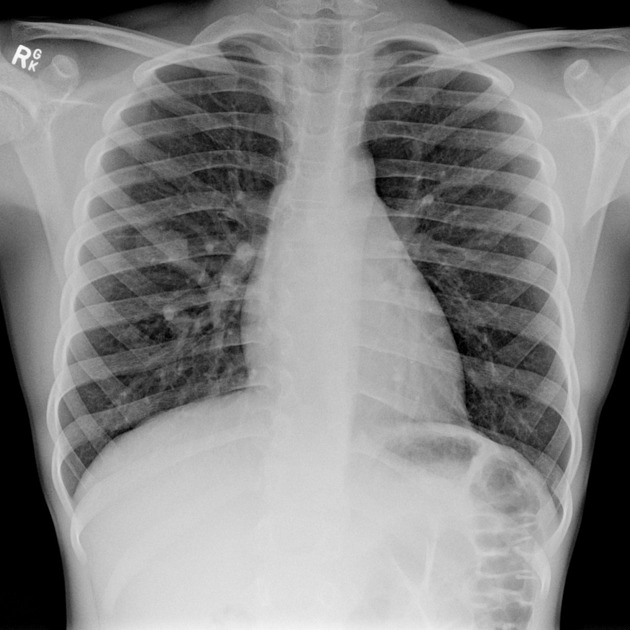

• CXR → AVMs